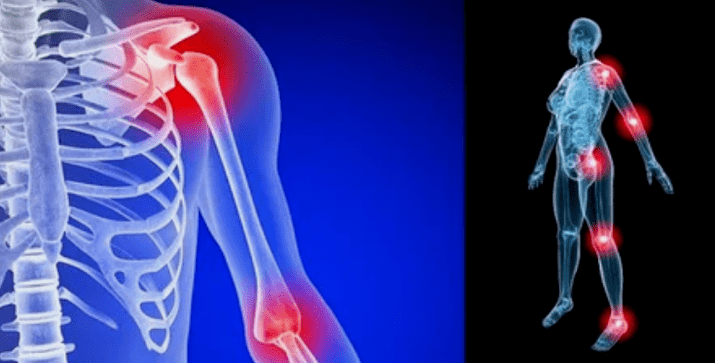

Las manifestaciones de la enfermedad difieren poco dependiendo de la localización, con mayor frecuencia los signos se reflejan en las rodillas, los hombros y las articulaciones de la cadera, debido a la alta carga.

La mayoría de las quejas se reducen a:

- dolor. Tienen baja gravedad en la etapa inicial, con agravación del estado de sensación se intensifica. Inicialmente, las articulaciones duelen solo después de despertarse, después de una luz cálida, las sensaciones desaparecen. Con el tiempo, los dolores aparecen por la noche, perturban mucho durante y después de caminar, correr, etc. en la última etapa, el síndrome de dolor persigue a una persona todo el tiempo;